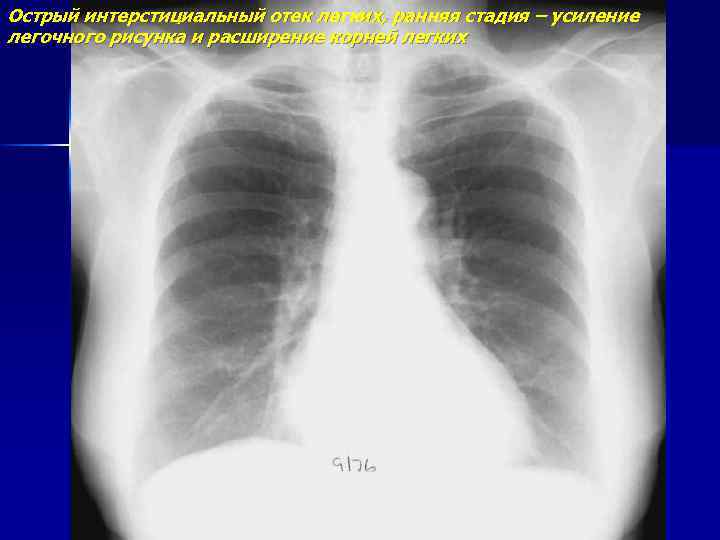

Острый интерстициальный отек легких, ранняя стадия – усиление легочного рисунка и расширение корней легких